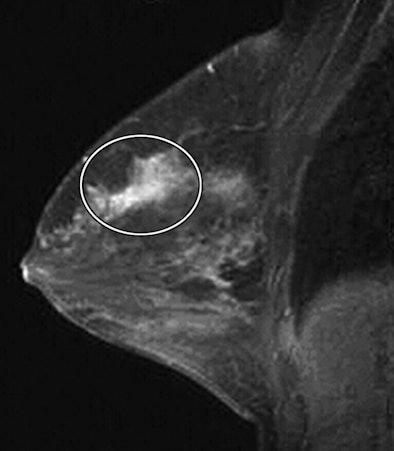

| Craniocaudal breast-specific gamma images of left (above left) and right (above right) breasts and mediolateral oblique images of left (below left) and right (below right) breasts show increased uptake at 12-o'clock position in right breast (arrows) as well as increased uptake in upper outer quadrant of left breast. |